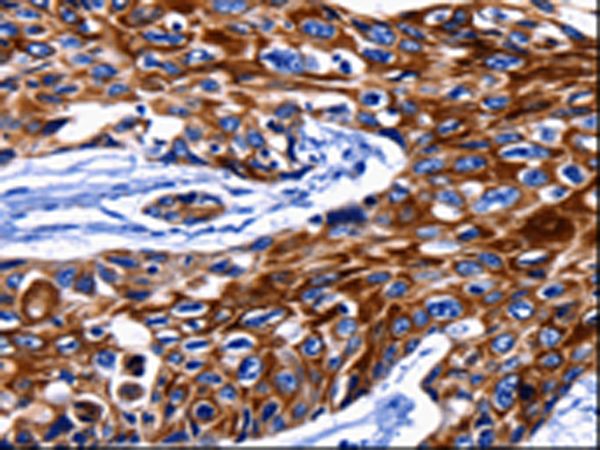

分类: 科研抗体货号: P10775别名: DRP3; ULIP; CRMP4; DRP-3; LCRMP; CRMP-4; ULIP-1应用: WB,IHC反应种属: Human, Mouse, Rat